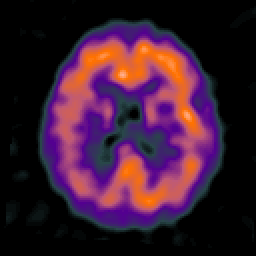

Alzheimer's disease: overlay -- Slice #16

[Home][Help][Clinical] Slice 16